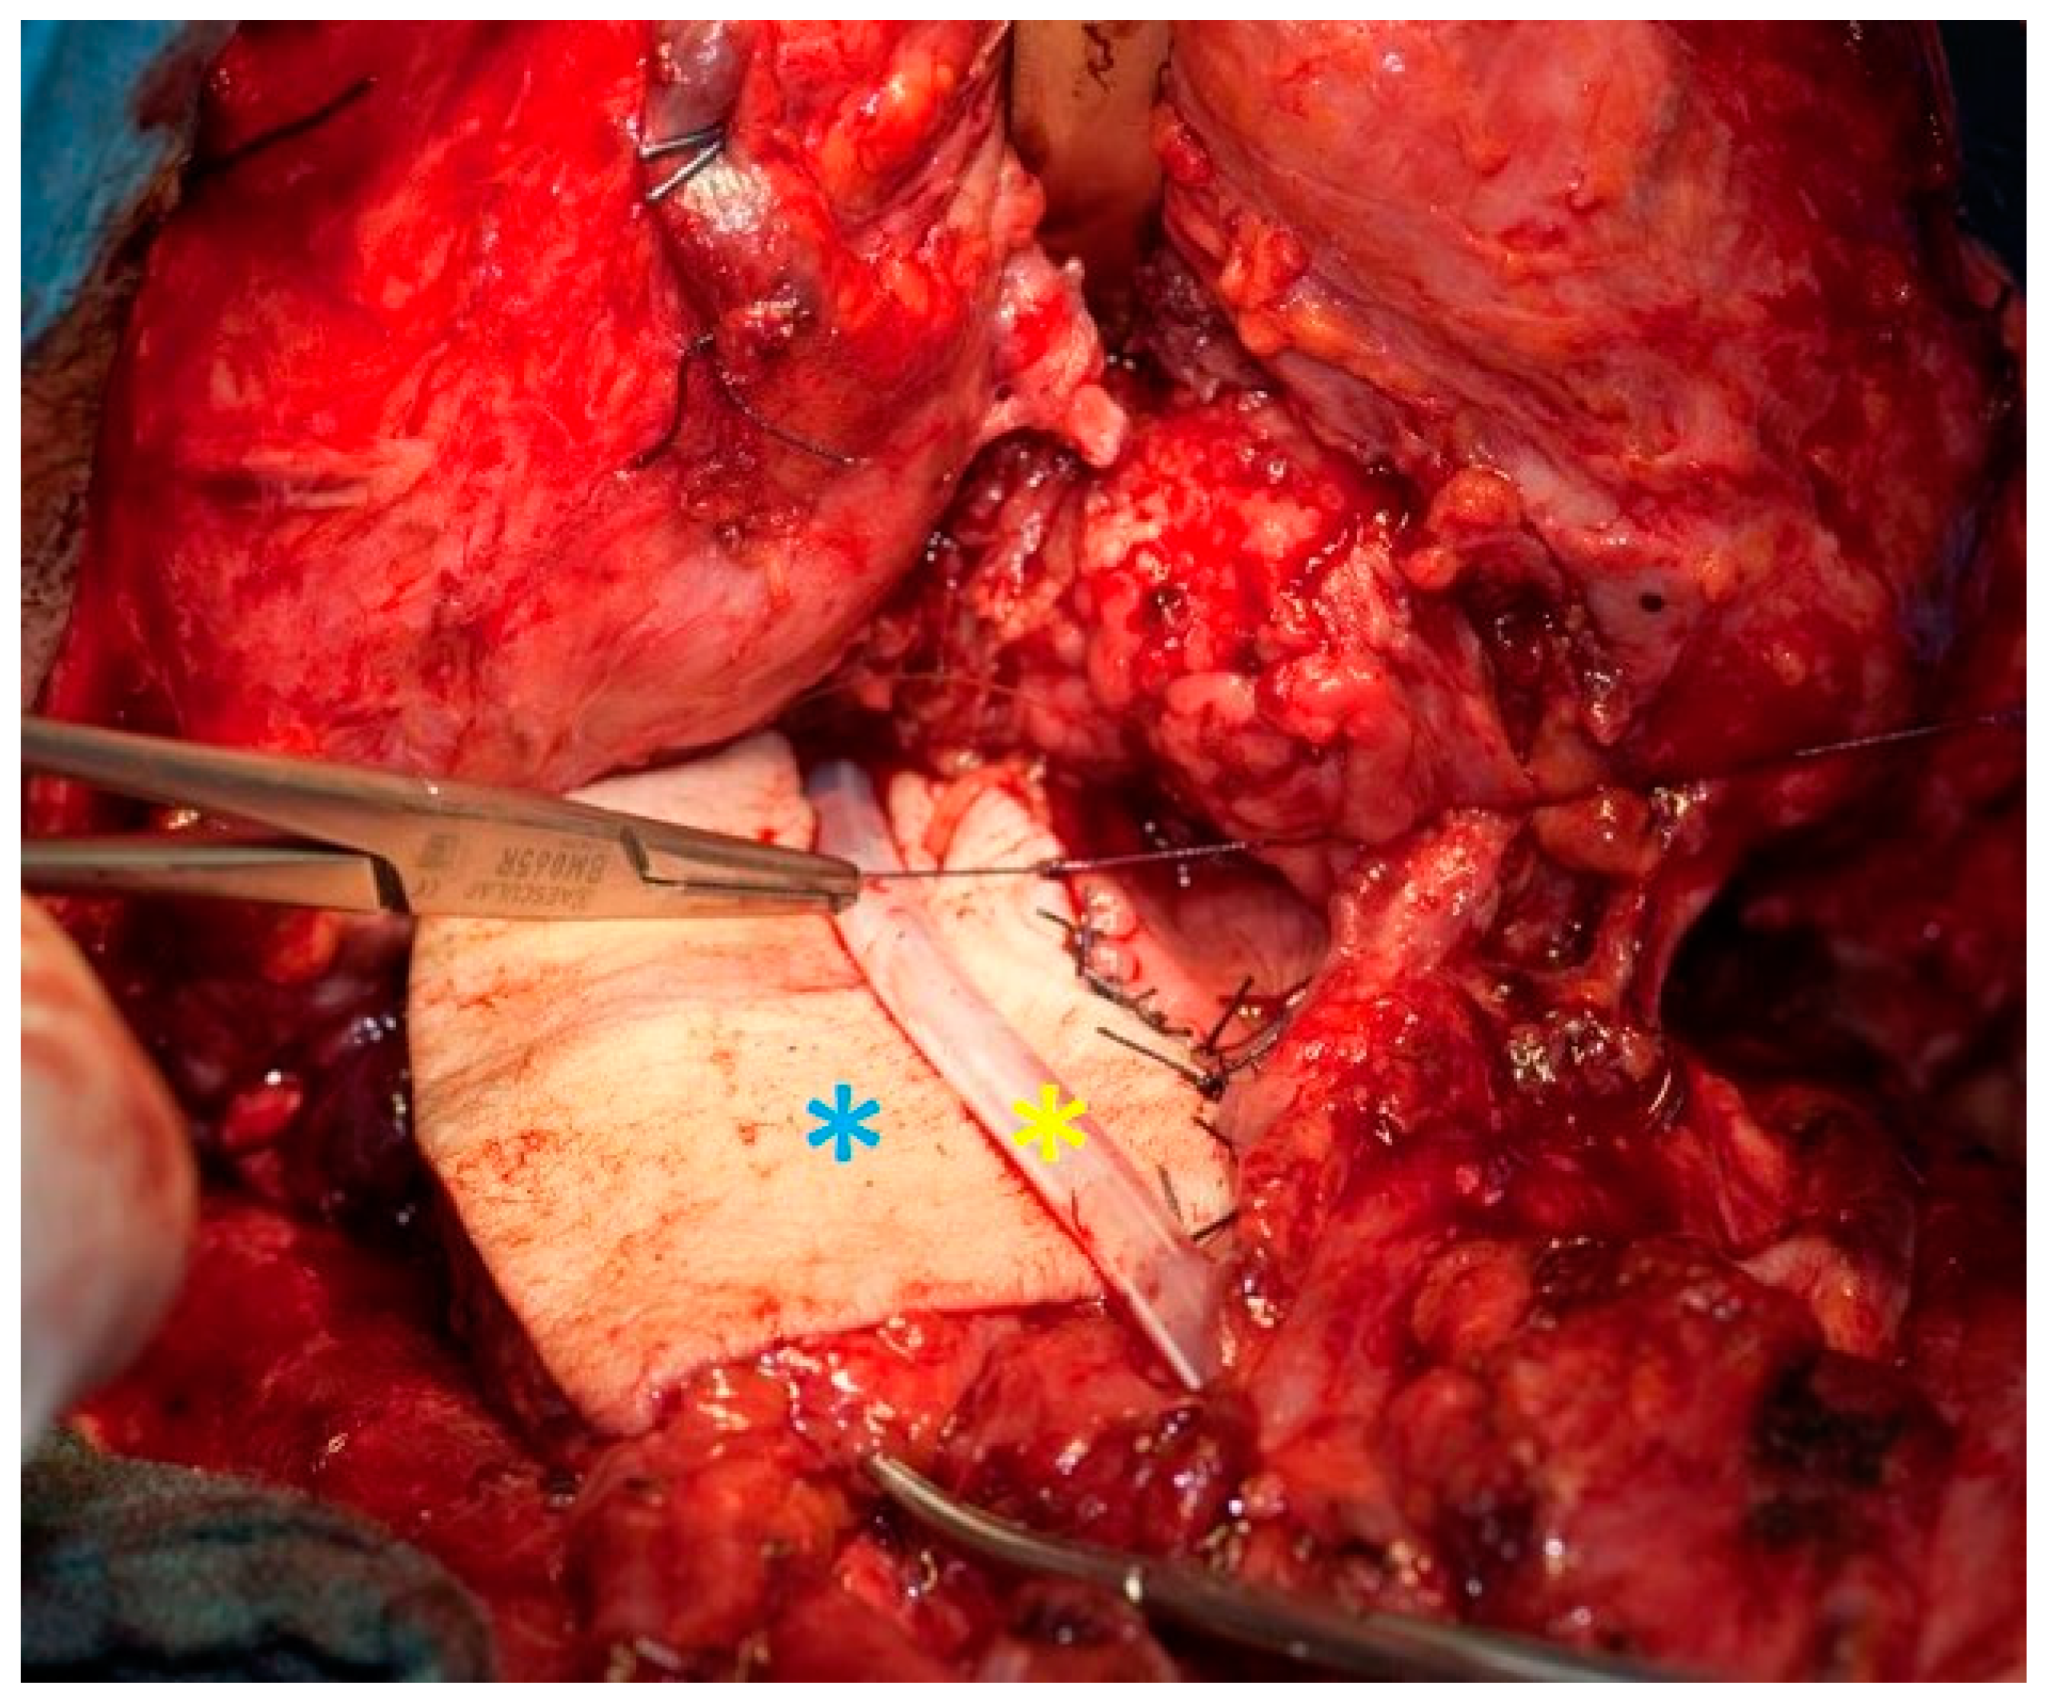

Figure 3.

Laryngopharyngectomy with pharyngeal reconstruction by a free microvascular anastomosed radialis graft (blue asterisk). Feeding tube in the middle (yellow asterisk).